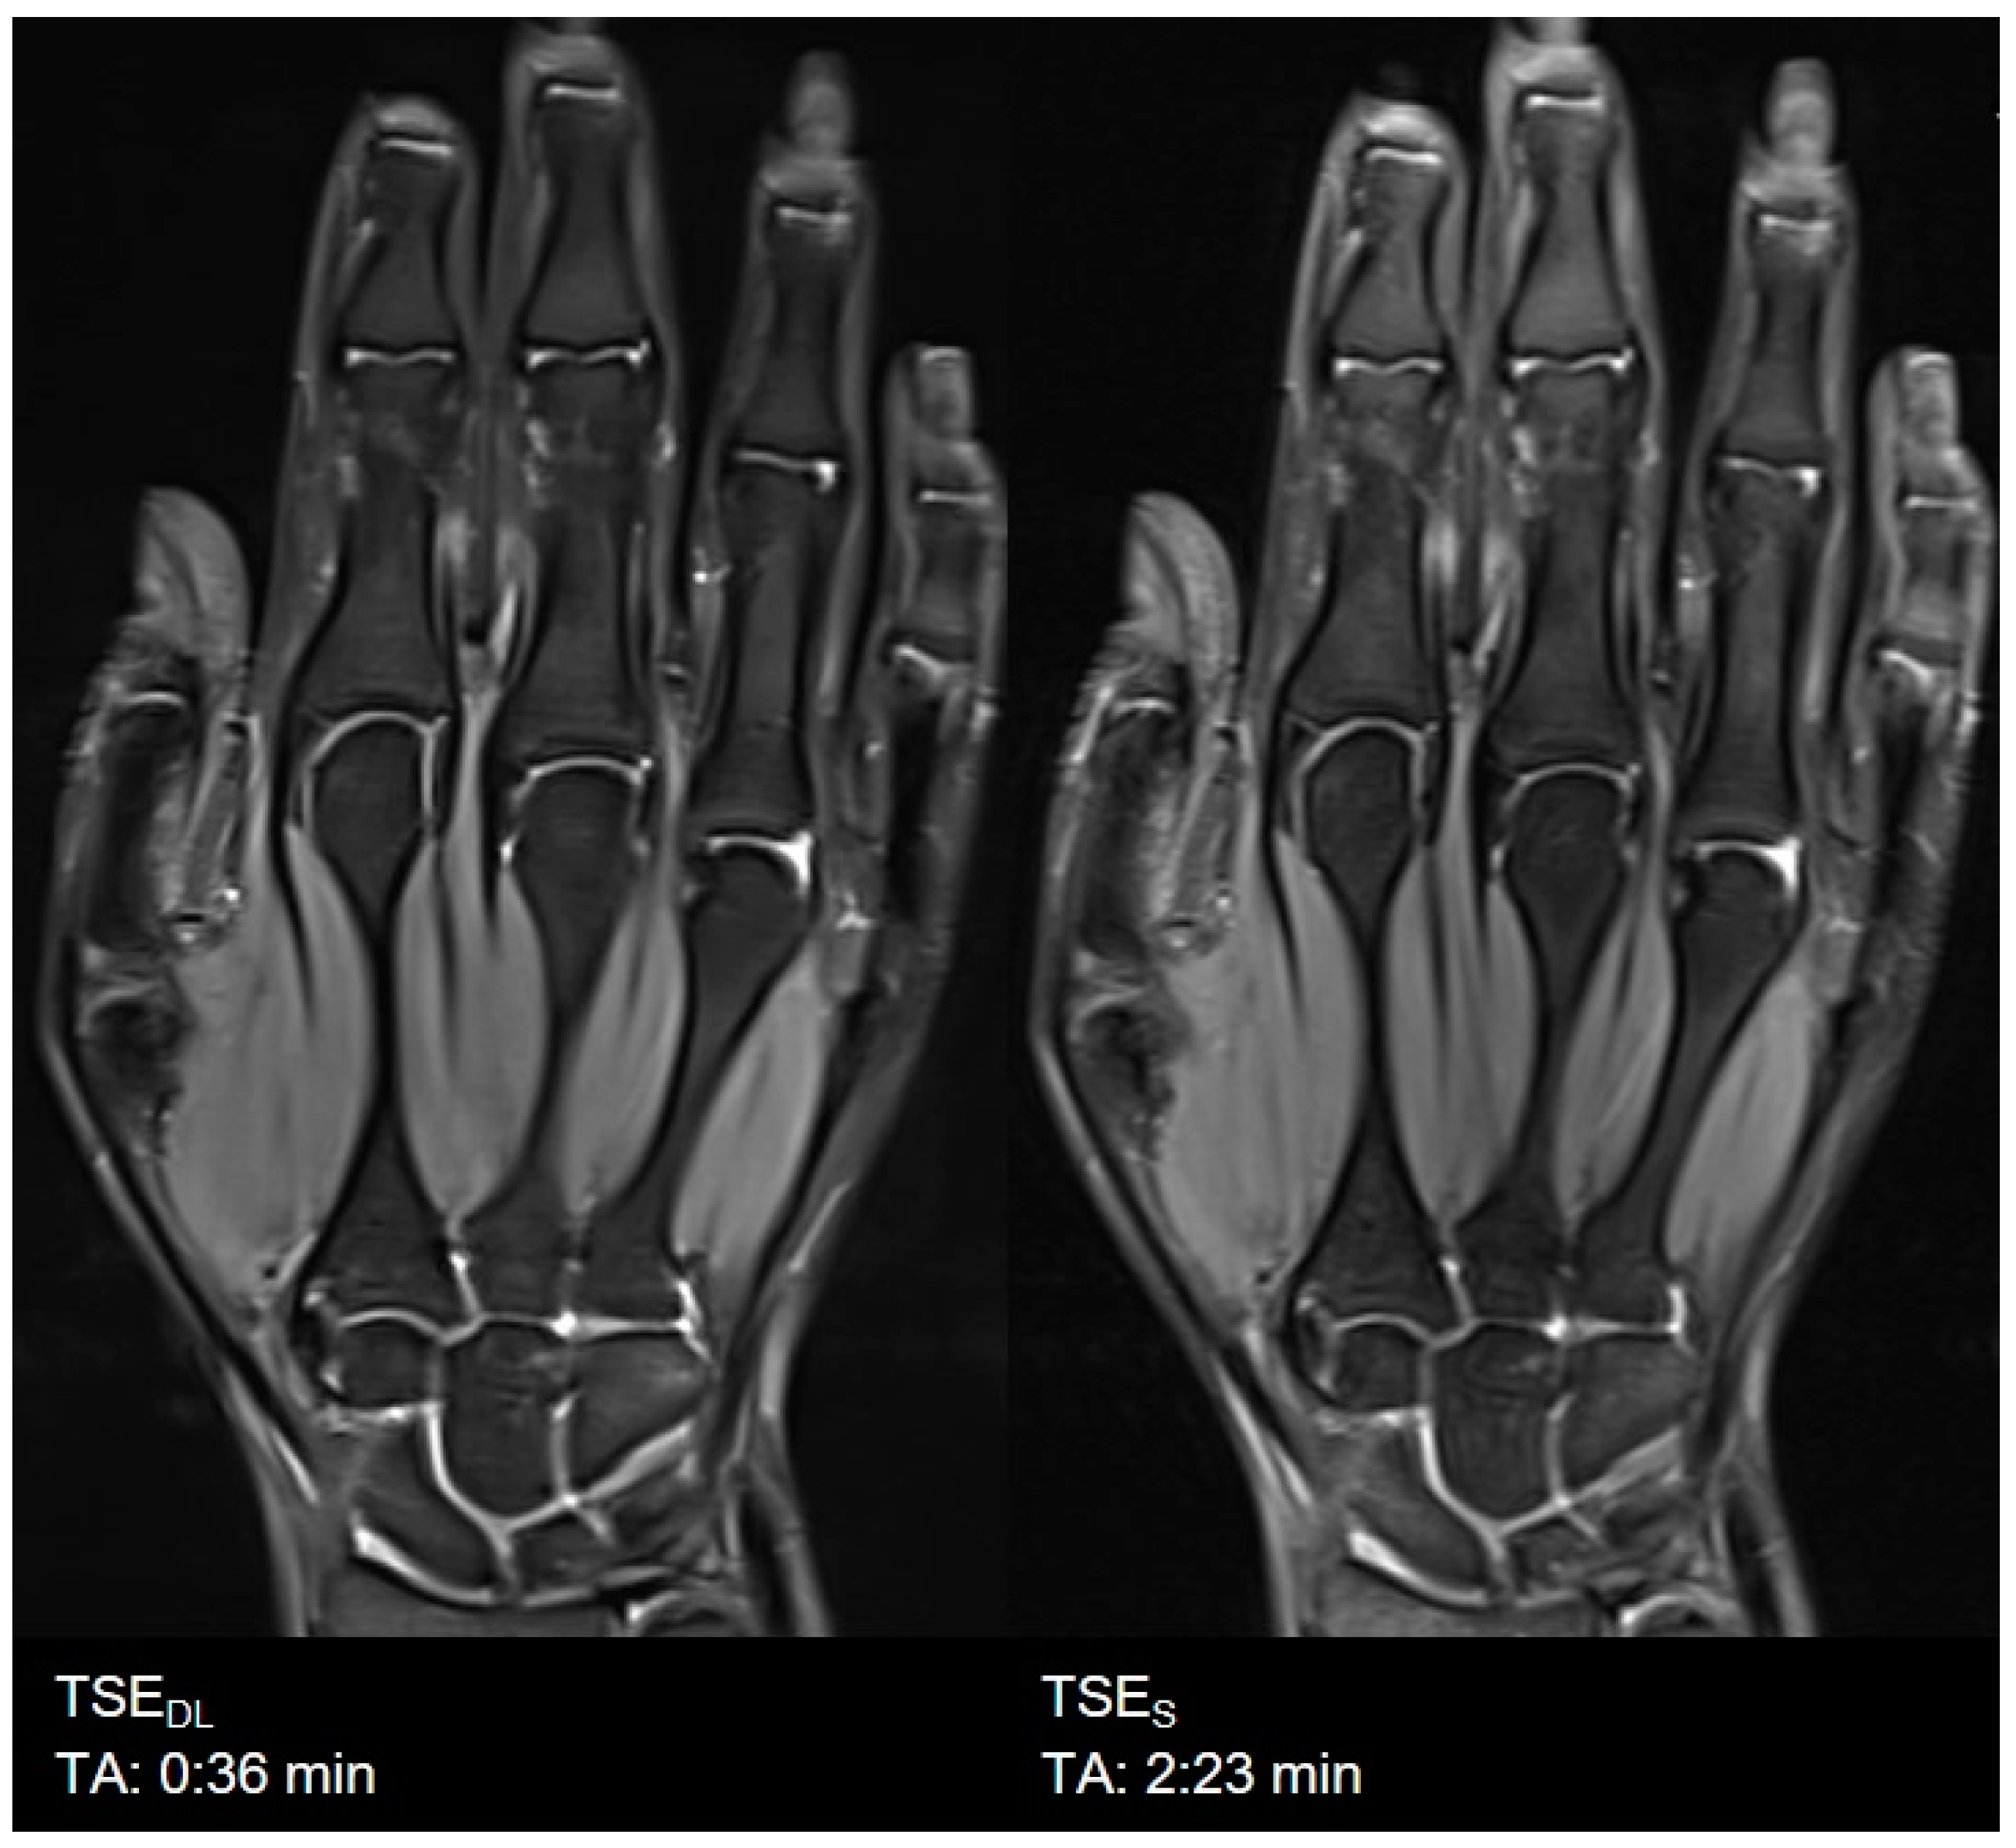

3. Results

3.1. Assessment of Image Quality

3.2. Assessment of Anatomical Structures